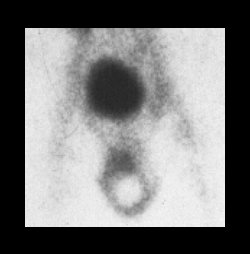

Sistema Urogenital

Cartera de servicios a nivel de estudios y exámenes especializados del sistema urogenital.